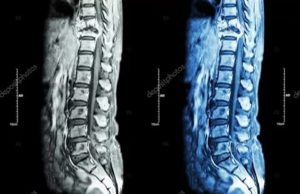

- Рентгенография позвоночного столба или отдельных его участков. К сожалению, этот доступный метод диагностики неспособен выявить метастазы на их раннем этапе развития.

- Для выявления неврологии МРТ является лучшим вариантом обследования. Магниторезонансная томография показывает не только аномалии позвонков и межпозвоночных образований, она также нужна для исследования нервных стволов и расположенных в области позвоночника сосудов;

- Компьютерная томография (КТ);

- Магнитно-резонансная томография (МРТ);

- Рентгенография позвоночного столба и органов грудной клетки — позволяет выявить литические очаги рака;